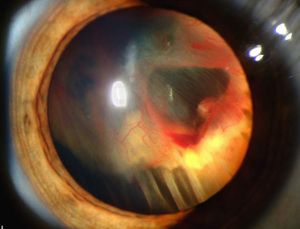

عندما تنزف القزحية ينصب الدم في الغرفة الأمامية ويسبب تشوش الرؤية إذا كان النزف خفيفاً. أما إذا كان النزف شديداً فإن الدم يملأ البيت الأمامي، وتزول الرؤية، وقد يرتفع الضغط داخل العين (زرق glaucome ثانوي) ويحدث ألم شديد واحتقان هدبي ووذمة في القرنية، وإذا اندخل الدم في لحمة القرنية تطلب مداخلة إسعافية.

التشخيص

يُشاهد النزف في الغرفة الأمامية بالعين المجردة، أو بالمصباح الشقي، فُتقّدر كميته ويُراقب ارتشافه كما يُراقب ضغط العين باستمرار.

المعالجة

إذا كان النزف قليلاً تكفي الراحة مع إعطاء الأدوية المرقئة والمسرعة لارتشاف الدم. أما إذا كان النزف غزيراً، وبدأ ضغط العين بالارتفاع فعندها لابد من التدخل الجراحي بغسل النزف من الغرفة الأمامية لمنع مضاعفات الزرق وارتشاح القزحية.